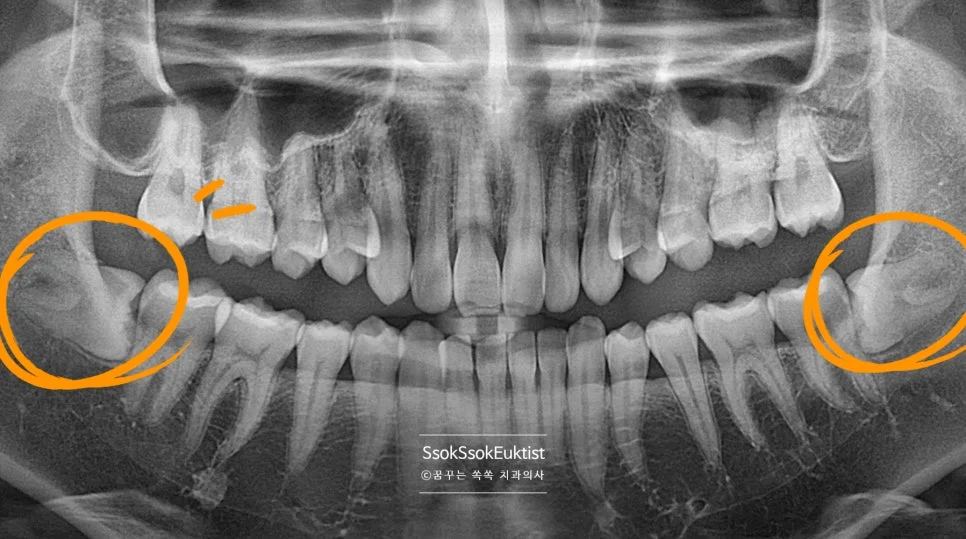

파노라마 엑스레이 — 상악과 하악 사랑니 위치 전체 확인

충치가 심하게 생긴 왼쪽 위아래 사랑니

충치가 심하게 생겨 사랑니 통증으로 오신 분인데요, 왼쪽 위아래 사랑니입니다.

중간 난이도 완전 매복 사랑니 파노라마 엑스레이

잇몸 하방에 완전히 묻혀 있는 완전 매복 사랑니입니다. 사랑니가 맹출 하면서 잇몸의 통증을 호소하는데요, 뒤의 턱뼈와의 공간이 부족하여 어차피 매복될 치아라 바로 발치를 말씀드립니다.